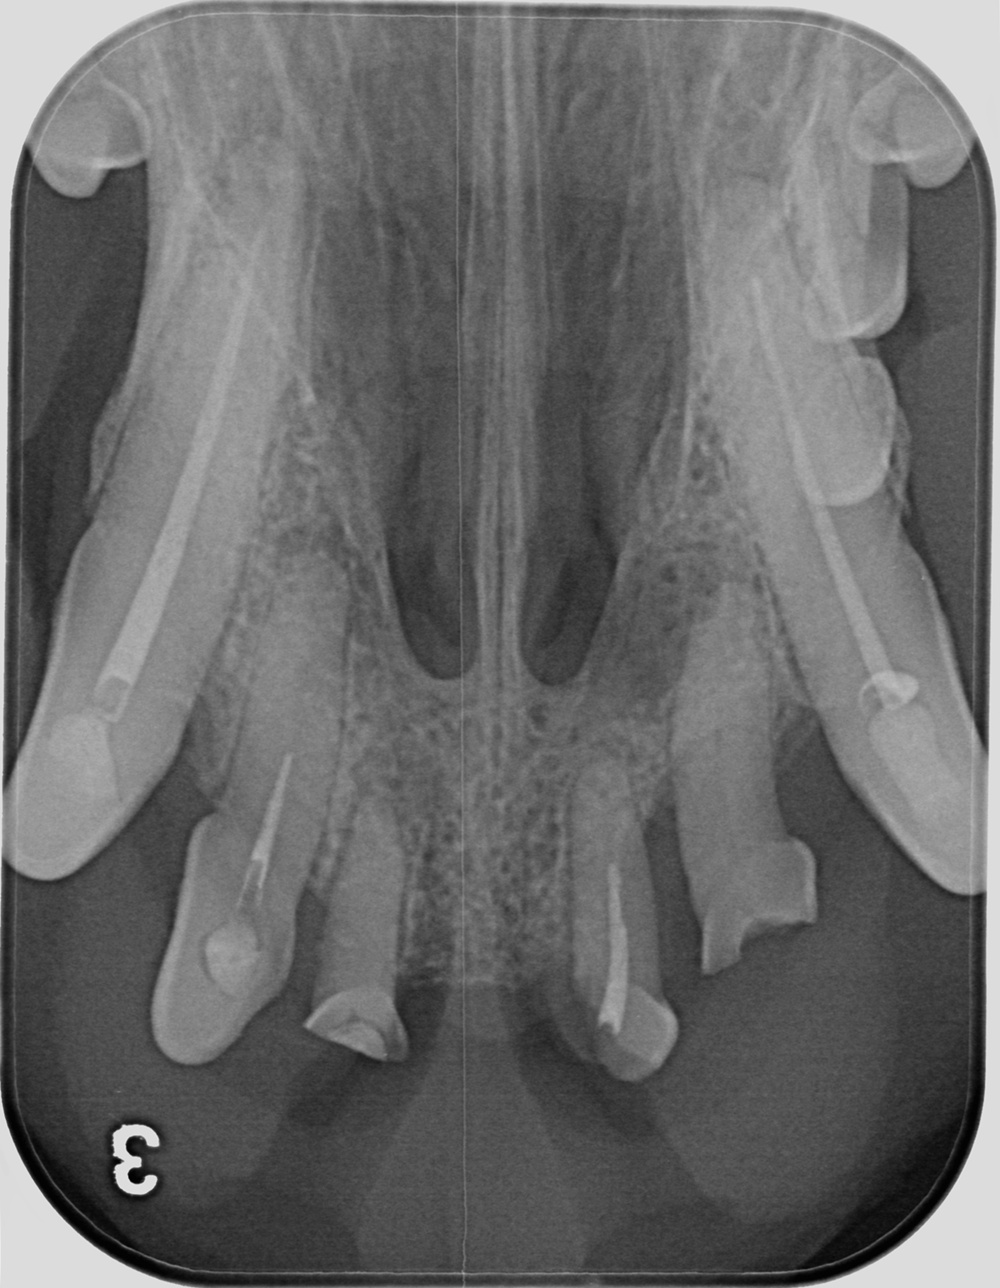

현재 수의치과학에서의 근관치료는 사람의 근관치료를 위해 개발되고 발전해 온 기구와 재료를 사용할 수밖에 없는 현실에 놓여 있다. 그러나 사람과 개, 고양이의 근관 해부학적 특성은 분명히 다르다. 따라서 이러한 기구와 재료를 개와 고양이의 근관 해부학에 맞게 적절히 변형(modification)하여 적용하는 것이 중요하다. 특히 사람에 비해 훨씬 복잡한 apical delta가 발달한 개와 고양이에서는 근단 1/3 부위를 얼마나 효과적으로 성형·세정·충전하는지가 높은 성공률을 좌우한다는 점이 최근 발표된 여러 문헌을 통해 확인되고 있다.